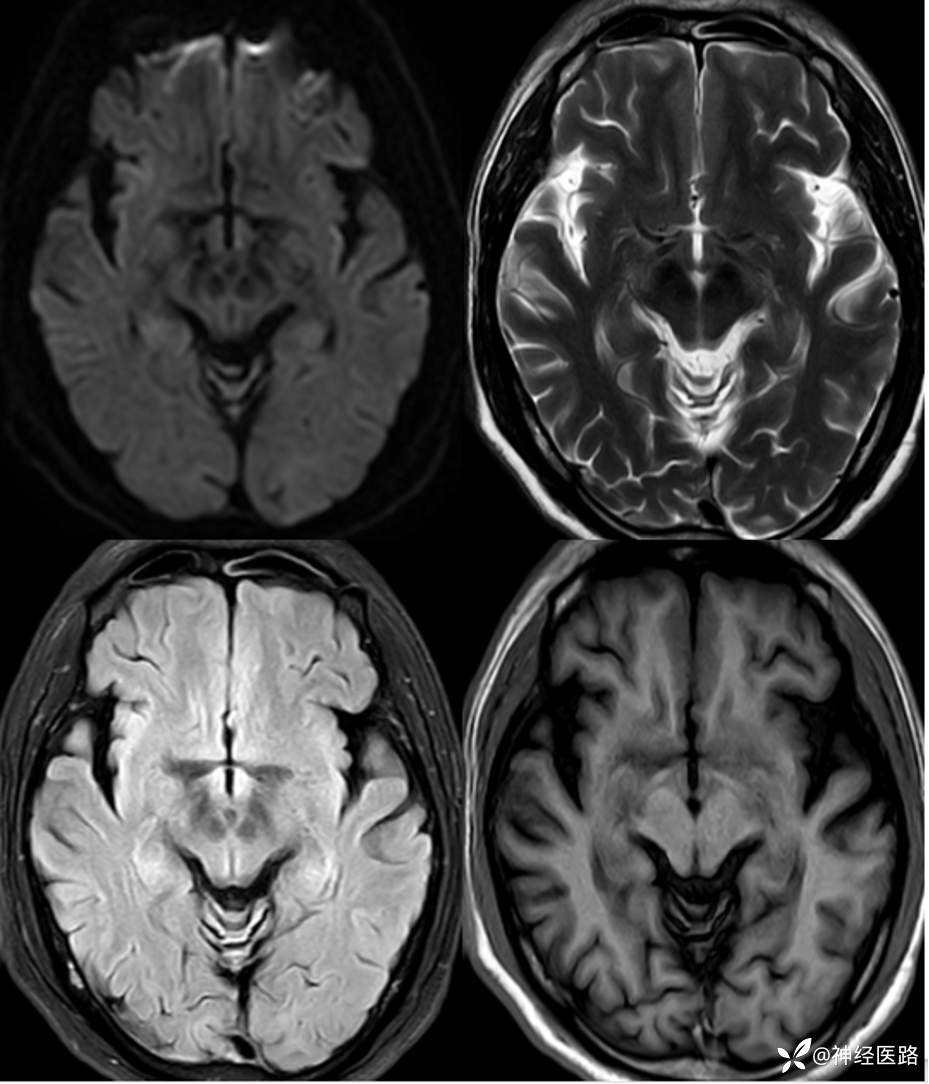

辅助检查:头部磁共振:1.颅脑DWI未见明显异常扩散受限。 2.脑白质高信号,脑萎缩。3.双侧上颌窦、双侧筛窦、双侧额窦炎。

两次影像对比